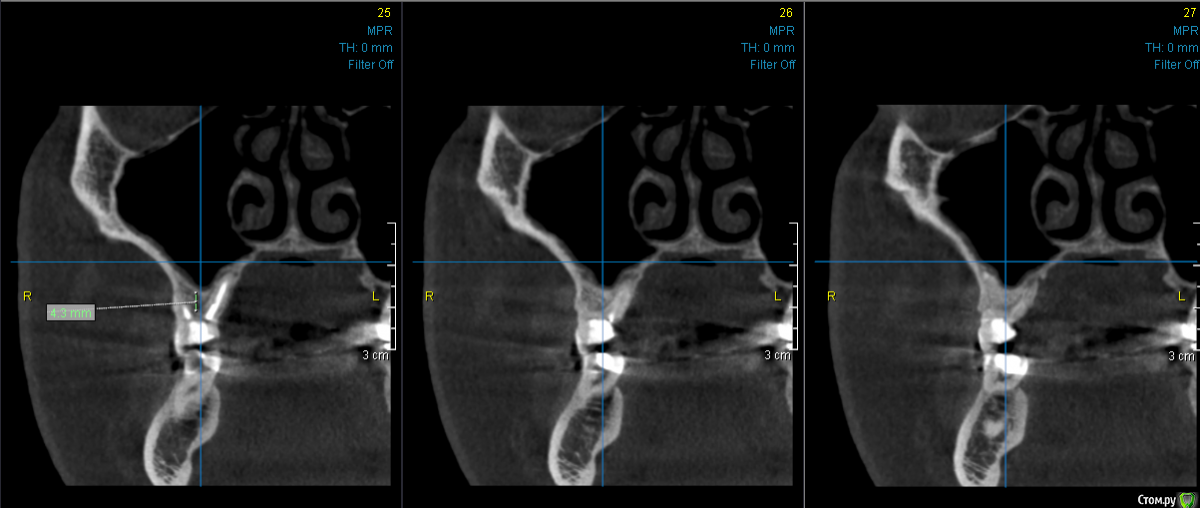

kramer Опубликовано 24 августа, 2018 Поделиться Опубликовано 24 августа, 2018 Коллеги, посоветуйте, пожалуйста. Лучше одномоментно + закрытый или одномоментно + открытый? Хотелось бы поставить 10-мм имплантат. Для ЗСЛ в клинике есть только остеотомы. Спасибо. Ссылка на комментарий

Карен Аванесов Опубликовано 24 августа, 2018 Поделиться Опубликовано 24 августа, 2018 Если 10мм открытый и сразу формирователь десны. 1 Ссылка на комментарий